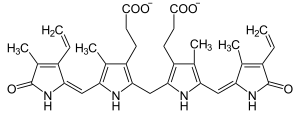

| Bilirubin | |

The conjugated hyperbilirubinemia is a result of defective endogenous and exogenous transfer of anionic conjugates from hepatocytes into bile.[8]

Impaired biliary excretion of bilirubin glucuronides is due to a mutation in the canalicular multiple drug-resistance protein 2 (MRP2). A darkly pigmented liver is due to polymerized epinephrine metabolites, not bilirubin.[9]

A hallmark of Dubin–Johnson syndrome is the unusual ratio between the byproducts of heme biosynthesis:

- Unaffected subjects have a coproporphyrin III to coproporphyrin I ratio around 3–4:1.

- In patients with Dubin–Johnson syndrome, this ratio is inverted, with coproporphyrin I being 3–4 times higher than coproporphyrin III. Analysis of urine porphyrins shows a normal level of coproporphyrin, but the I isomer accounts for 80% of the total (normally 25%).